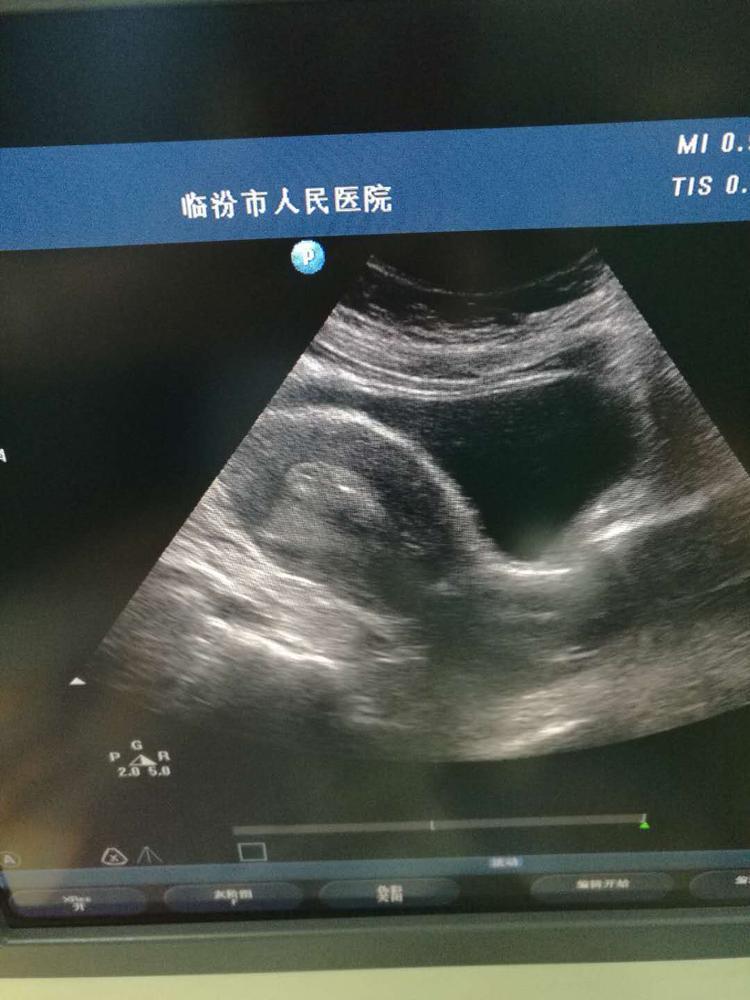

我院首例高齡不孕女性凍融胚胎移植成功妊娠

近日,我院生殖醫(yī)學中心完成首例高齡不孕女性通過試管助孕技術(shù)-凍融胚胎技術(shù)成功妊娠。患者42歲,因雙側(cè)輸卵管阻塞,在我院生殖醫(yī)學中心進行試管嬰兒技術(shù)助孕治療,2017年10月,她成功取卵10枚,并形成7枚胚胎,移植2枚,冷凍5枚,當月移植未孕,于2018年1月行凍融胚胎移植術(shù),目前化驗血HCG4720.29miu/ml,提示宮內(nèi)妊娠。這是我院生殖中心首例高齡不孕女性通過試管助孕技術(shù)-凍融胚胎技術(shù)獲得成功妊娠,是生殖醫(yī)學團隊共同努力的結(jié)果。